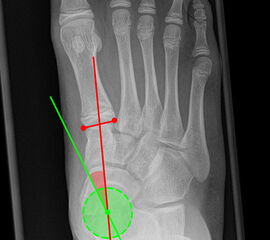

Beurteilung eines Metatarsus adductus

Medial wird eine Linie von der medialen Begrenzung des TMT1-Gelenks und der medialen Begrenzung des Talonavikulargelenks (TN) gezeichnet. Auf der lateralen Seite des Fußes wird eine zweite Linie von der lateralen Begrenzung des Calcaneocuboid-Gelenks (CC) zur lateralen Begrenzung des TMT5-Gelenks gezeichnet. Die Mittelpunkte beiden Linien werden verbunden (blau). Der Winkel zwischen der Achse des Os metatarsale II (rot) und dem Lot auf Verbindungslinie (grün) ist ein Maß für die Stellung des Vorfußes zur Fußwurzel. Dieser Wert dient zur Charakterisierung eines Pes adductus. Ein Pes adductus kann zu einem normwertigem Intermetatarsale I/II Winkel führen, obwohl klinisch eine ausgeprägte Hallux valgus Deformität vorliegt 8. (Norm: ±13° 9.